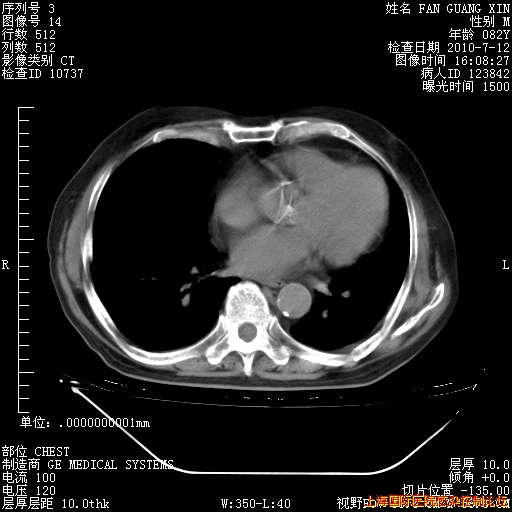

今天CT

整整相隔30天的肺部CT好像有所好转啊。甲强龙减量第3天,需要观察体温。

海管,自昨日你和我通完话后,不知您岳父消化道症状有无缓解?体温怎样?阅读7.12日胸部ct,个人认为目前激素治疗是有效的,甲强龙减量是适宜的。因在抗痨治疗,需密切观察肝功、肾功能和血常规。不过,老年、长期住院和大量使用激素,很担心菌群失调发生